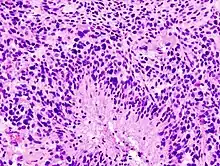

Glioblastomas are characterized by the presence of small areas of necrotizing tissue that are surrounded by anaplastic cells. This characteristic, as well as the presence of hyperplastic blood vessels, differentiates the tumor from grade 3 astrocytomas, which do not have these features.

Glioblastoma (histology slide)